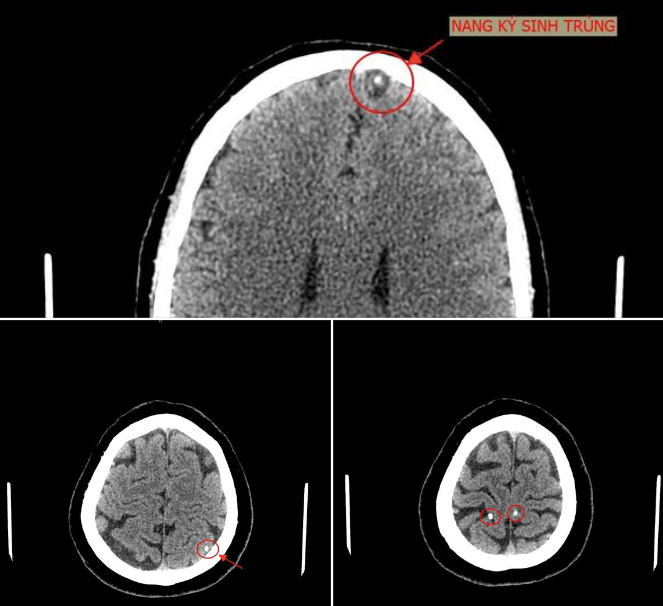

Hình ảnh chụp cắt lớp cho thấy trong sọ não bệnh nhân có hình ảnh nang ký sinh trùng. (Ảnh: BVCC)

Bệnh nhân vào Trung tâm Y tế Tân Sơn (Phú Thọ) ngày 23/6. Bác sĩ khoa Chẩn đoán hình ảnh kết luận trong sọ não bệnh nhân có hình ảnh nang ký sinh trùng (ấu trùng sán não). Bệnh nhân cho biết bản thân có thói quen ăn đồ sống như gỏi cá.